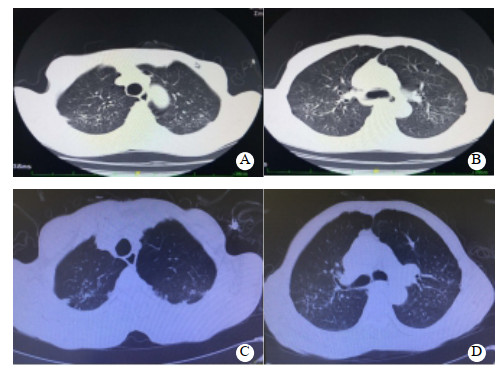

1 资料与方法患者66岁,男性,农民,2020年6月15日下午饮酒(量不详)后误服“虫螨腈”30~50 mL,后昏睡不醒,次日醒酒后出现恶心、呕吐非咖啡渣样胃内容物1次,腹泻3次,为稀水样便,总量少,伴心悸、气促、出汗,无胸闷、胸痛、腹痛,无发热、肌肉酸痛、肌颤、抽搐,家属急送双柏县人民医院急诊科就诊。既往体健,无高血压、糖尿病、心脏病、肺部疾病、外伤等病史。查体:体温36.5℃,心率86次/min,呼吸20次/min,血压102/67 mmHg(1 mmHg=0.133 kPa),血氧饱和度95%(未吸氧);GCS评分15分;全身皮肤出汗,双侧瞳孔等大等圆,直径2.5 mm,光反射灵敏;口唇无发绀;颈软无抵抗,两肺呼吸音清晰,未闻及干湿性啰音;心律齐,未闻及杂音;腹平软,无肌紧张,无压痛及反跳痛,肝脾未触及,肠鸣音正常;双下肢无浮肿,四肢肌力、肌张力正常,病理征未引出。入院后予急诊留观处理,予“奥美拉唑、果糖二磷酸钠、环磷腺苷葡胺、维生素C、维生素B6、氯化钾”静滴及补液对症治疗。心电图示窦性心律,ST-T正常。相关辅助检查见表 1。患者治疗第2天,腹泻缓解,无呕吐发生,正常进食,小便正常。治疗3 d后(6月19日)患者心悸、气促加重,伴大量出汗,收住ICU治疗。查体:体温36.7℃,心率117次/min,呼吸21次/min,血压107/66 mmHg,血氧饱和度95%(鼻导管吸氧3 L/min);GCS评分15分;全身皮肤出汗较多,余无特殊改变。心电图示窦性心律,偶发房性期前收缩,T波低平,见图 1A。肺CT示双肺多发纤维增殖灶,慢性支气管炎,肺气肿,双肺多发肺大疱,见图 2A~B。入住ICU后的相关辅助检查见表 1。继续予上述治疗,并予“地塞米松磷酸钠注射液10 mg/d”静脉注射。经治疗,患者心悸、气促无明显缓解,仍有大量出汗,6月22日转至本院急诊科进一步诊治。查体:体温37.2 ℃,脉搏94次/min,呼吸27次/min,血压103/58 mmHg,血氧饱和度94%(鼻导管吸氧3 L/min);GCS评分15分;全身大汗淋漓,全身皮肤黏膜完好,无破溃,双侧瞳孔等大等圆,直径2.5 mm, 光反射灵敏;口唇无发绀;呼吸急促,心肺腹查体无异常;四肢肌肉无挤压痛,四肢肌力、肌张力正常,病理征未引出。心电图示窦性心律,T波低平,见图 1B。测随机血糖为5.9 mmol/L。肺CT与前相仿,见图 2C~D。相关辅助检查见表 1。本病例资料报道已获得患者家属的知情同意。

| A、B:中毒第5天;C、D:中毒第8天 图 2 患者肺CT结果(示双肺多发纤维增殖灶,慢性支气管炎,肺气肿,双肺多发肺大疱) |